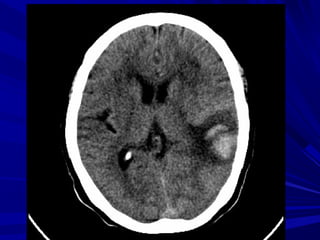

Buøi vaên L., Nam, 45 tuoåi, Xuaát huyeát nhaân beøo-bao trong (P) coù

traøn maùu naõo thaát

Buøi Vaên L., Nam, 45 tuoåi, Xuaát huyeát nhaân